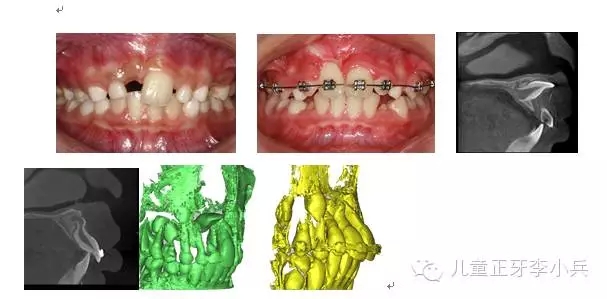

4.III類骨性畸形的早期矯治:傳統(tǒng)的功能矯形概念是在兒童青春發(fā)育高峰前期開(kāi)始。對(duì)于骨性III類的矯形治療的開(kāi)始時(shí)間,國(guó)內(nèi)外一直存在爭(zhēng)議。華西兒童早期矯治??圃诳偨Y(jié)本科III類骨性矯治的療效后,認(rèn)為III類骨性的矯形矯治在第一橫磨牙萌出時(shí)(6歲)開(kāi)始必在青春發(fā)育高峰前期(9歲)時(shí)開(kāi)始能得到更多的骨性改變。(圖5,III類骨性的早期功能矯形治療)必須強(qiáng)調(diào)的是,早期功能矯形治療必須保持到恒牙列初期(12歲)以維持矯形治療的效果,避免由于遺傳的影響造成的矯形治療的復(fù)發(fā)。43.webp.jpg

圖 5 骨性III類錯(cuò)合的早期矯治,保持持續(xù)到兒童發(fā)育結(jié)束;